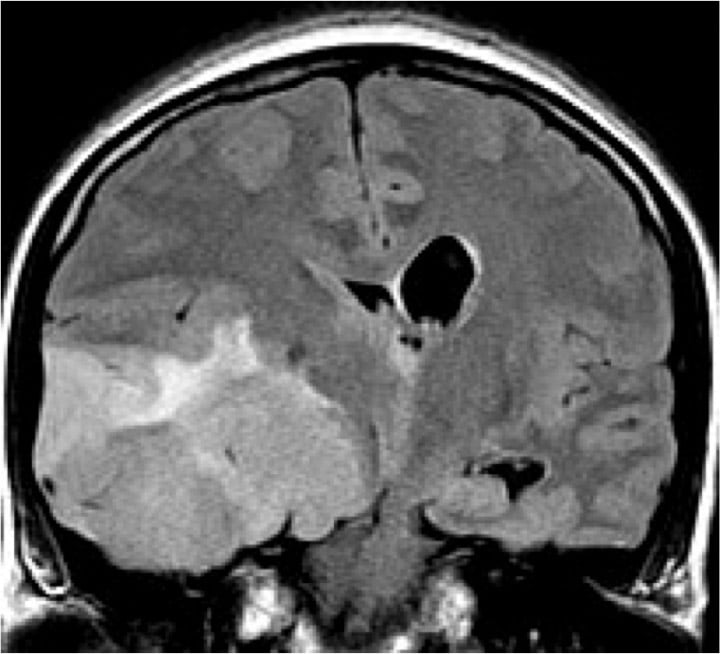

- Brain and spine tumors

- 8 clinical MR systems

- 1 research 3T MR system